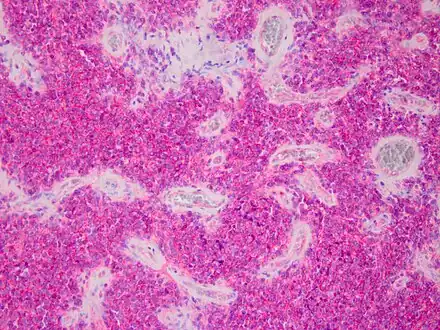

Micrograph of an H&E stained section of a peripheral PNET.

Peripheral PNET

The peripheral PNET (pPNET) is now thought to be virtually identical to Ewing sarcoma:

"Current evidence indicates that both Ewing's sarcoma and PNET have a similar neural phenotype and, because they share an identical chromosome translocation, they should be viewed as the same tumor, differing only in their degree of neural differentiation. Tumors that demonstrate neural differentiation by light microscopy, immunohistochemistry, or electron microscopy have been traditionally labeled PNETs, and those that are undifferentiated by these analyses have been diagnosed as Ewing's sarcoma."[6]